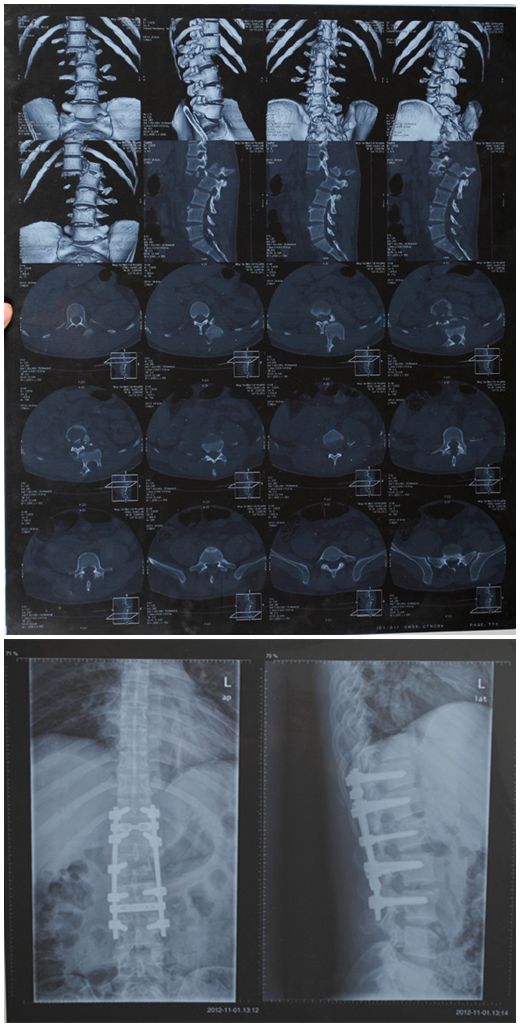

然而,比起车祸更为残酷的现实是,一年前的车祸引起的双腿截瘫致腰2椎骨折,脊髓横贯性损害,之后的曾哥也曾在当地医院进行过脊柱手术治疗。遗憾的是,手术显然对曾哥没起到太大的作用,外伤及手术后1年来双下肢肌力为0级,不能站立更不能行走的事实让他原本平静的生活一下子跌到了谷底。

骨折后和骨折术后